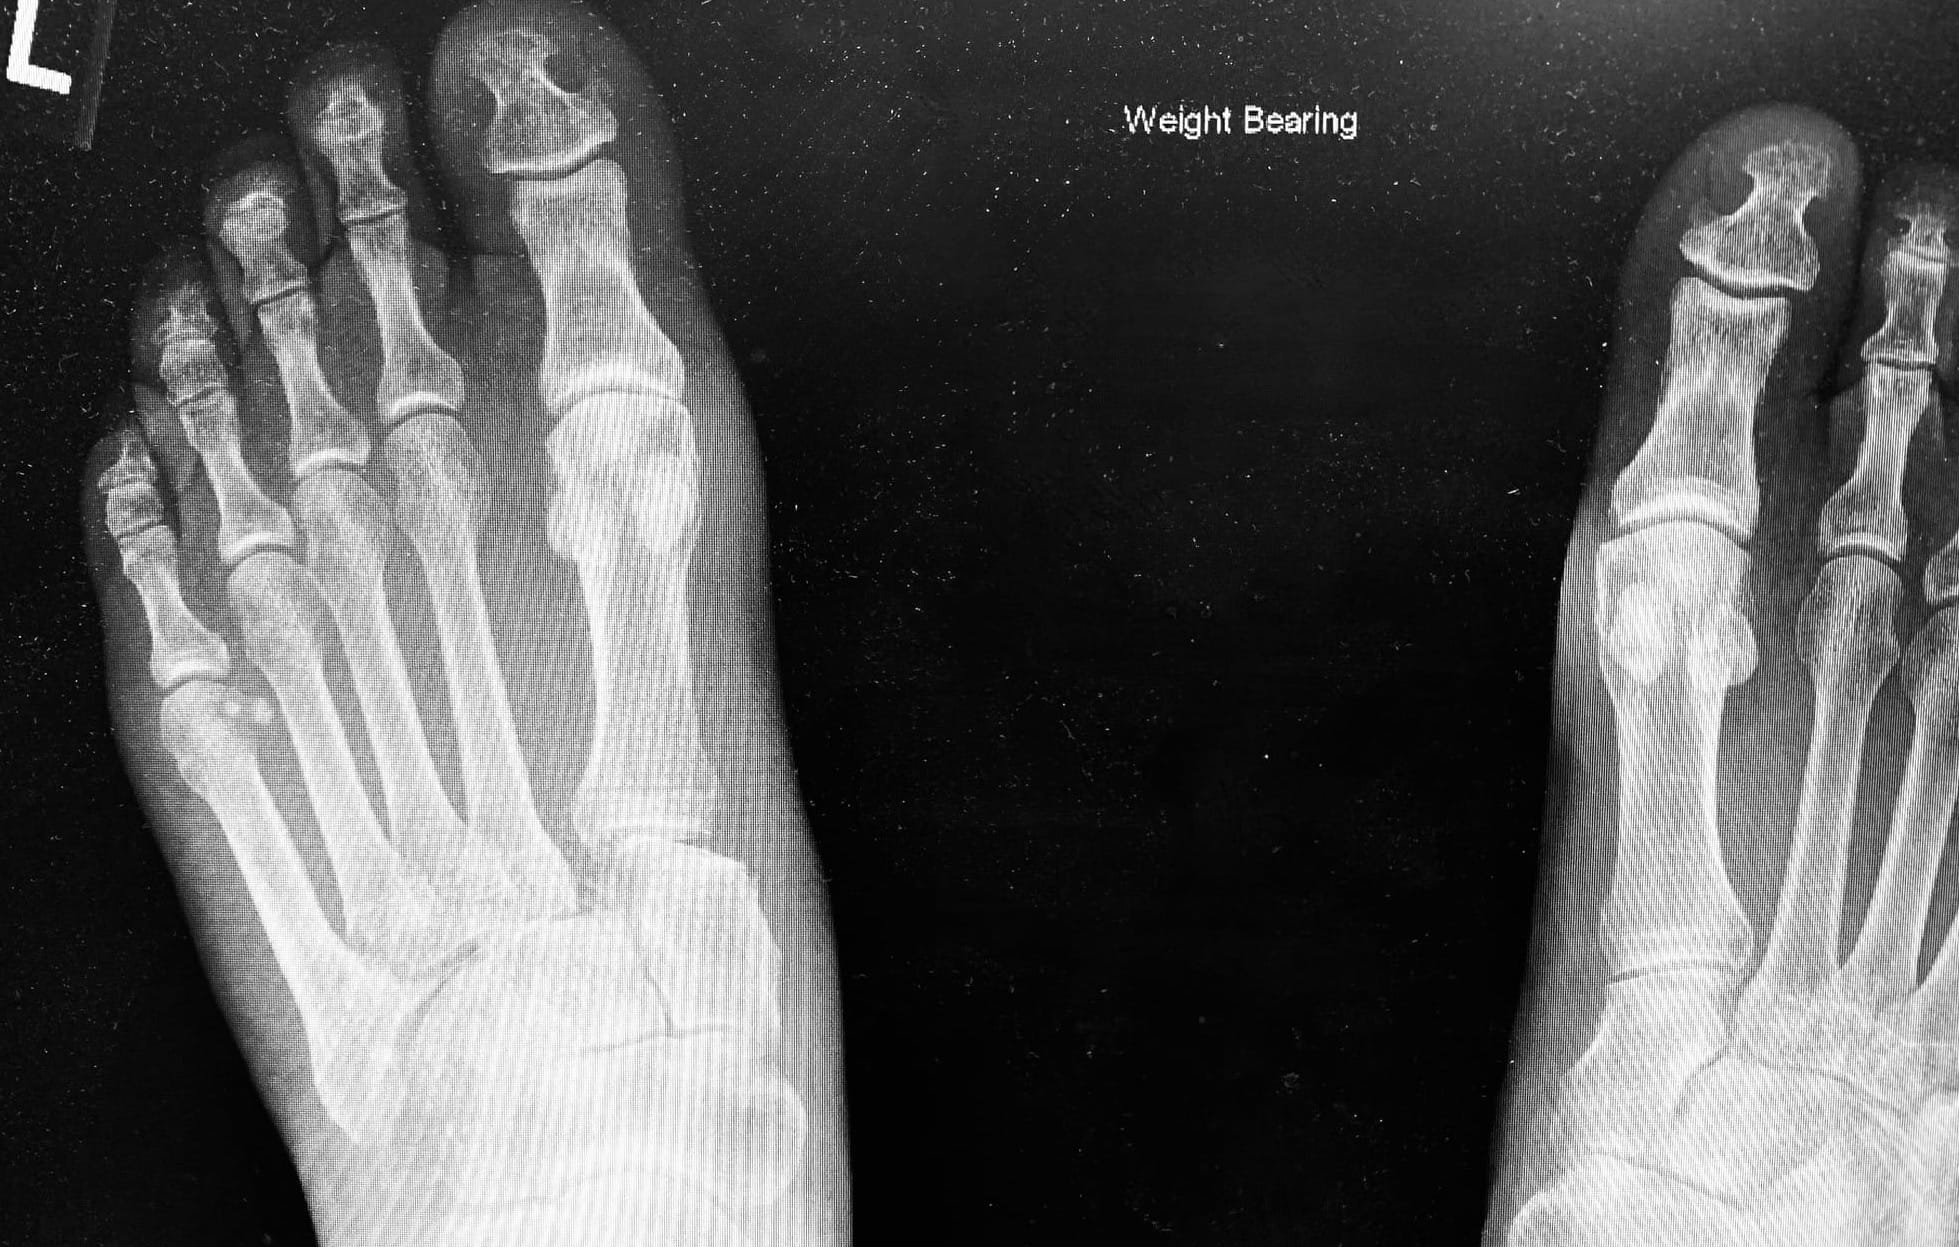

*Non-weight bearing x-rays miss subtle diastasis between the 1st and 2nd metatarsal bases in up to 50 % cases.5

*Bilateral weight-bearing views detect about 85% of injuries and should be requested if there is any suspicion of possible Lisfranc injury.5

*Other key subtle X-ray changes to look for are (a) malalignment of the 2nd tarsometatarsal joint and (b) a dorsal step on the lateral view due to dorsal displacement of the 2nd metatarsal base.6